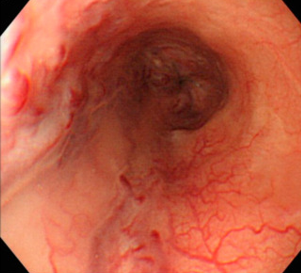

Κολονοσκόπηση. Ευδιάκριτα ευρήματα ισχαιμικής κολίτιδας (Ευγενική παραχώρηση Dr. V. Penopoulos)